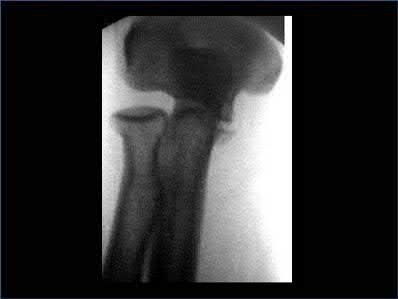

A 12-year-old male sustains an ulnar fracture with an associated posterior-lateral radial head dislocation. After undergoing closed reduction, the radiocapitellar joint is noted to remain non-concentric. What is the most likely finding?

In pediatric Monteggia fractures the annular ligament is commonly interposed in the radiocapitellar joint.

Bado initially described and classified Monteggia fractures. The most common injury pattern is an extension type 1 with anterior radial head dislocation and apex anterior ulnar shaft fracture. The apex of the ulna fracture determines the direction of the radial head subluxation or dislocation. Adults typically require ORIF of the ulna. These fractures in children are often treated non-operatively with closed reduction if the ulna fracture is transverse and stable. Type III is the one most commonly associated with irreducibility of the radial head because of interposition of the annular ligament. The incidence of posterior interosseous nerve injury is high with this lesion. The nerve deficit usually completely resolves rapidly and spontaneously.

Tan et al reviewed their treatment of 35 children with Type I and Type III Monteggia fractures. All radial heads were explored and the interposed annular ligament was stretched out of the joint space. They noted that none of the patients had any recurrent dislocation or subluxation.

Ring et al in their review stress the importance of an anatomic reduction of the ulna to restore the reduction of the radial head.